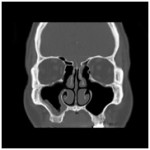

Chronic rhinosinusitis (CRS) is persistent and symptomatic even after optimal medical or surgical management, in 5-25% of cases. In spite of widely open sinus cavities that are ventilated and drain readily to the nasal cavity, the mucosa is still inflamed, infected, and/or edematous, often with gross polyposis.

| Figure 1a and 1b. Persistent sinusitis despite widely open sinus cavities | |